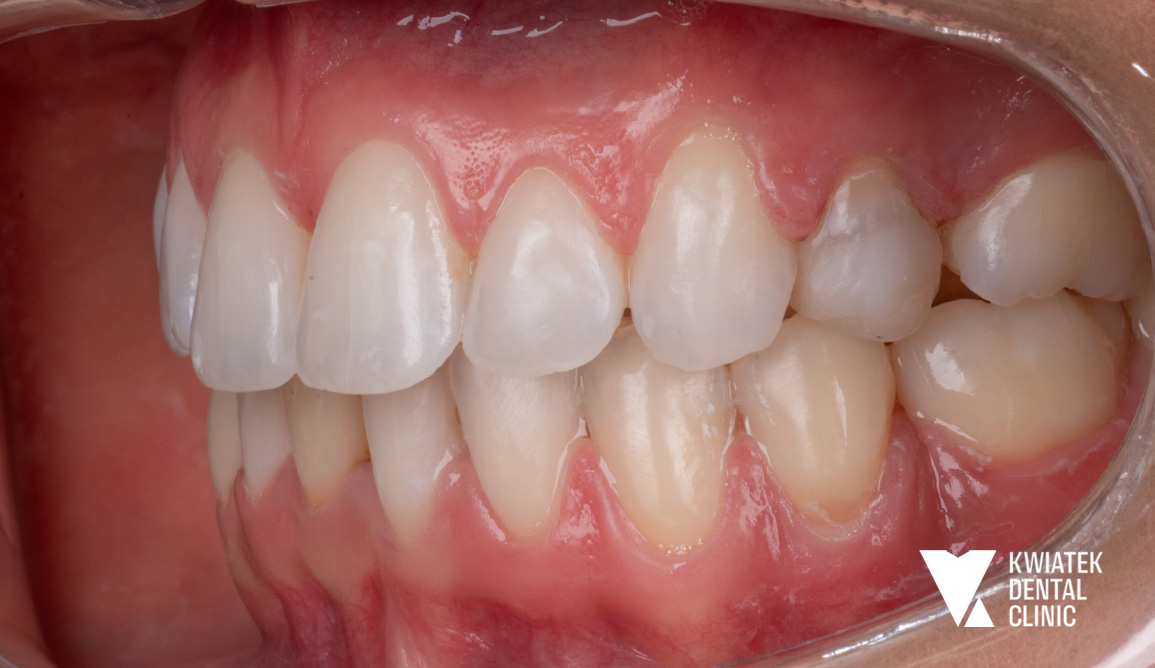

PRZED

Szczegółowa diagnostyka, obejmująca badanie kliniczne oraz zdjęcie panoramiczne, wykazała rozległe potrzeby lecznicze. Zidentyfikowano:

• wyraźne stłoczenia zębów, szczególnie w łuku dolnym

• zaburzenia zgryzu oraz brak miejsca na odbudowy implantologiczne

Diagnostyka ortodontyczna potwierdziła dodatkowo przesunięcie linii pośrodkowej oraz niewystarczającą przestrzeń w łukach zębowych, co wymagało precyzyjnego planowania leczenia.